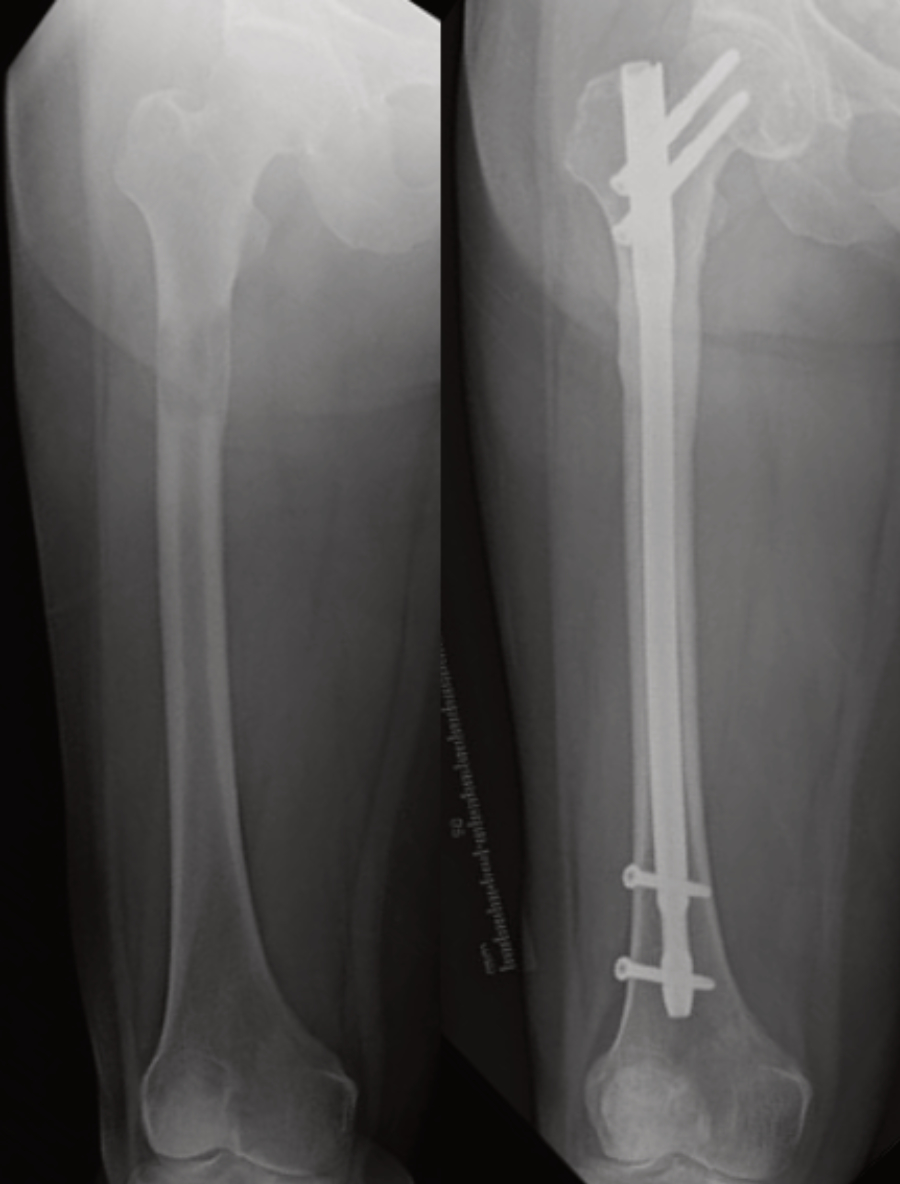

The aim of surgery is to prevent fractures from occurring, or to treat that fracture. A combination of clinical evaluation, X-rays and advanced scans are used to assess fracture risk. If the risk is estimated to be high, preventative surgery is offered, usually in the form of the insertion of a metal implant to reinforce the bone. Occasionally, the cancer affected segment of bone is removed and replaced with a metal implant; the complete removal of metastatic deposits (metastatectomy) reduces the risk of local cancer recurrence and may improve survival. The strategy is particularly useful if there is a single metastasis, the metastasis is poorly responsive to other forms of treatment, and/or if the patient has a long life expectancy. As cancer patients are now living for many years, it is important that the surgery should be sufficiently durable.

Figure 2: (L) Pre-operative X-ray shows a metastatic deposit from lung cancer with a high risk of pathological fracture. (R) Post-operative X-ray shows a titanium intramedullary nail used to reinforce the bone and prevent fracture.